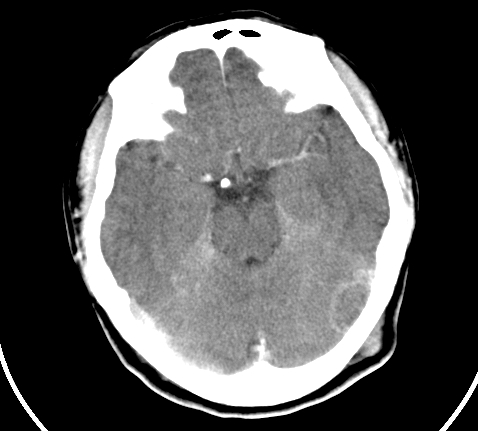

标题: CT23915:女 20岁 全身长疙瘩三年 今日多体位查 看看吧 [打印本页]

标题: CT23915:女 20岁 全身长疙瘩三年 今日多体位查 看看吧

神经纤维瘤病

支持神经纤维瘤。

支持 神经纤维瘤病。